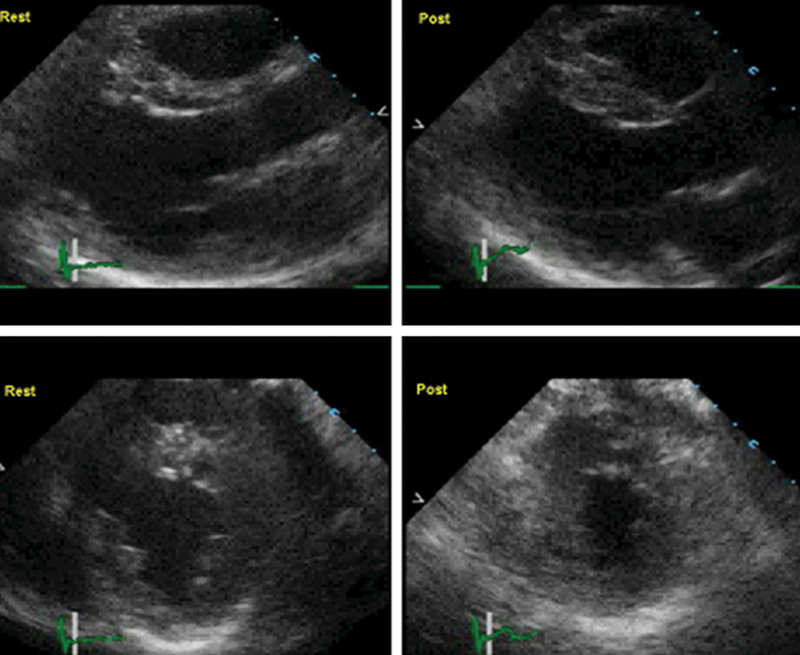

فحوصات تشخيصية لبعض امراض القلب والشرايين التاجية